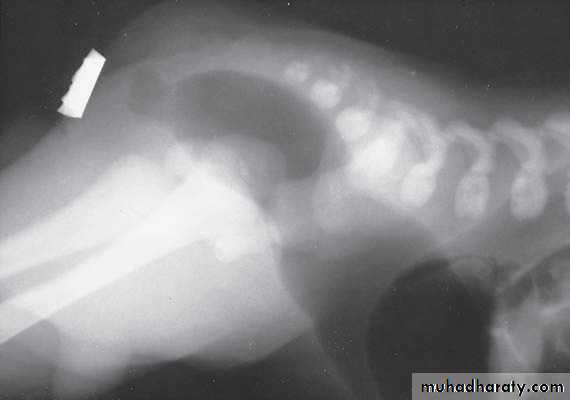

Scaphoid abdomen

Oesophageal Atresia and Tracheo-Oesophageal Fistula,